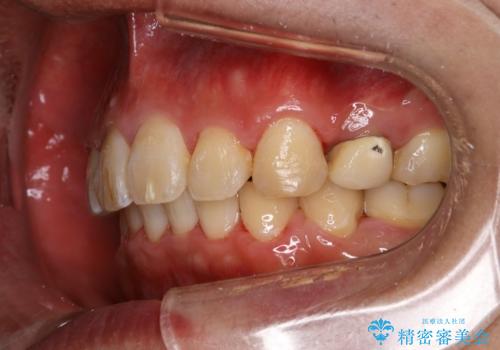

出っ歯、ガタつきの改善 ワイヤー矯正治療

- 上顎前歯の突出感と下顎前歯のガタつきが主訴で来院されました。

出っ歯とガタつきの改善を行うには抜歯が必要と診断し、上下左右第一小臼歯を抜歯する計画を立てました。